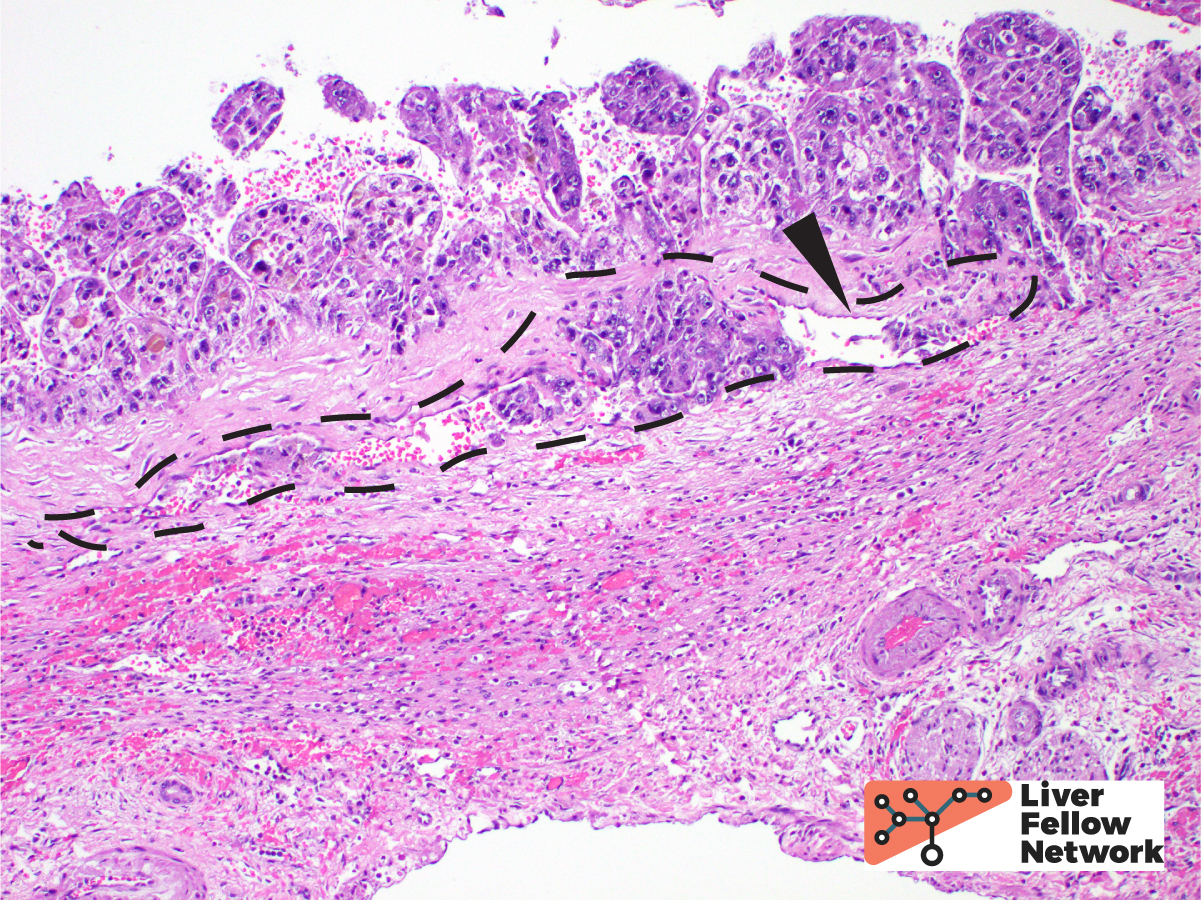

HCC is often treated by ablation or radioablation prior to surgical resection (Figure 9). In such cases, the role of the pathologist is not only to confirm the diagnosis, but to report on response to therapy and provide additional prognostic information (such as presence of lymphovascular invasion, Figure 10).

The differential diagnosis for hepatocellular carcinoma can be broad, depending on the clinical context (age and sex of the patient), composition of the background liver, and presence or absence of possible metastatic disease. Hepatic adenoma is an important differential consideration, most often in young or middle-aged females. Hepatic adenoma should only show hepatic plates of 1-2 cells thickness and should not demonstrate any significant cytologic atypia. Focal nodular hyperplasia is a benign, tumor-like lesion that is thought to be a proliferative/hyperplastic response to localized abnormal blood flow. In addition to showing normal hepatic plate thickness in the lesion which is surrounded by fibrous septa that may form a central scar, focal nodular hyperplasia shows a characteristic “map-like” staining pattern when stained for glutamine synthetase by immunohistochemistry. Regenerative nodules, often seen in cirrhosis can mimic a mass lesion; however, portal tracts should be identified within the nodule. Primary intra-hepatic cholangiocarcinoma is another primary malignancy that may be considered. Cholangiocarcinoma (a topic of a future LFN post), should show malignant gland formation, usually has evidence of mucin production, and frequently causes a markedly fibrotic and inflammatory response from the normal liver around it, also known as a desmoplastic stromal response. Separating HCC from metastatic tumors will rely on knowledge of the patient’s previous clinical history, if known, and use of lineage-specific protein markers via immunohistochemistry to identify the site of origin.